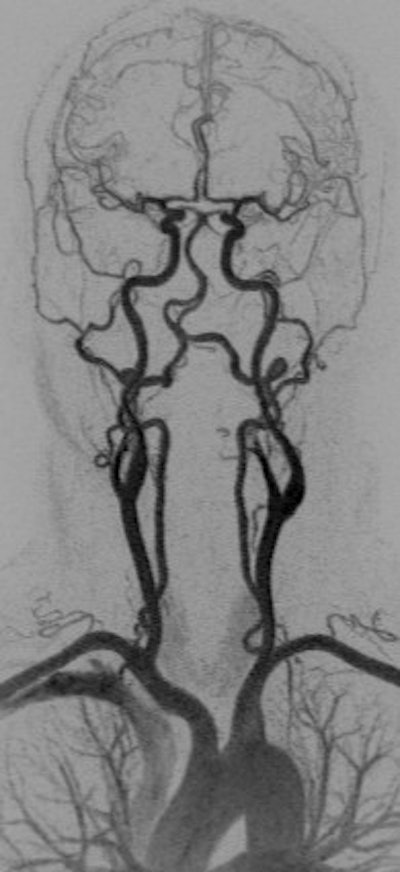

A 45-year-old woman experienced a transient ischemic attack. Coronal anterior inverted MIP (left) and posterior oblique volume-rendered (right) images from a high spatial resolution CE-MRA. The examination was performed by distributing a multiple array of coils over a large FOV (450 mm) to cover the entire supra-aortic arteries from the aortic arch to the vertex on a 3-tesla MR system. After IV injection of 0.1 mmol/kg (approximately 8 ml), the entire 3D dataset was obtained with isotropic voxel size of 0.8 mm³ during acquisition time. Note segmental irregularity and beaded appearance of the cervical segment of the left internal carotid artery compatible with fibromuscular dysplasia. All images courtesy of Dr. Kambiz Nael."The higher the baseline [signal-to-noise ratio], the more the potential for contrast dose reduction, so that 3-tesla field strength, multichannel RF architecture and high relaxivity contrast agents may support aggressive dose reduction strategies," the authors wrote. "Attention to detail in contrast infusion and image acquisition protocols is mandatory for reproducibility and quality control. Finally, time-resolved MRA with ultralow-dose contrast is likely to play an important role in patients at elevated risk of NSF."